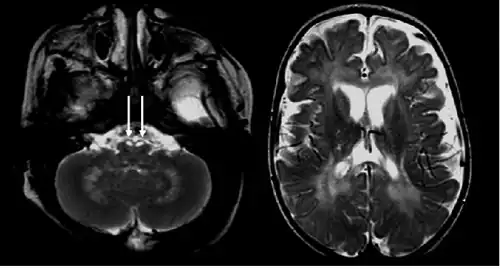

Diagnosis

There are a few ways to help pinpoint the presence of Krabbe disease. Newborn screening for Krabbe disease includes assaying dried blood cells for GALC enzyme activity and molecular analysis for evidence of GALC enzyme mutations. Infants displaying low enzyme activity and/or enzyme mutations should be referred for additional diagnostic testing and neurological examination.[13] 0-5% GALC enzyme activity is observed in all symptomatic individuals with Krabbe disease.[7] High concentration of psychosine in dried blood spots may also be identified as a marker for Krabbe disease.[14] A 2011 study discovered that individuals with Krabbe disease, more so in later-onset individuals, tend to have an abnormal increase in CSF protein concentration.[15]

The disease may be diagnosed by its characteristic grouping of certain cells (multinucleated globoid cells), nerve demyelination and degeneration, and destruction of brain cells. Special stains for myelin (e.g., luxol fast blue) may be used to aid diagnosis.